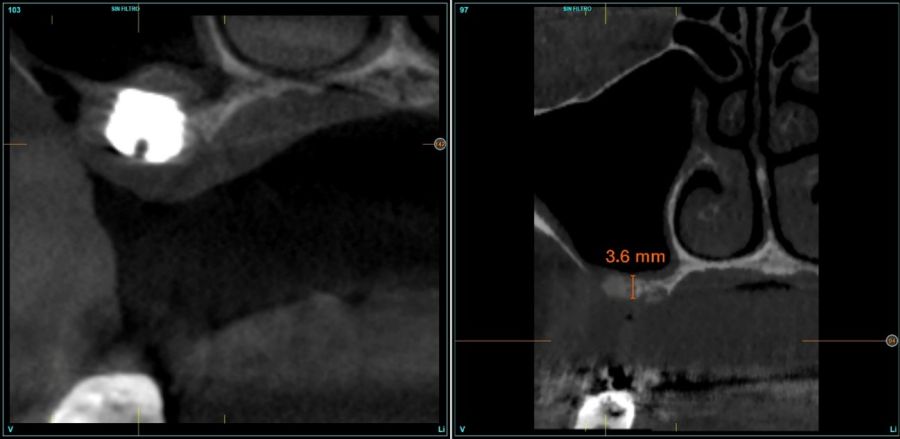

Fueron reclutados de forma retrospectiva pacientes en los que se llevase a cabo una inserción de implantes dentales de 4,5 mm de longitud en crestas óseas residuales de hasta 4,5 mm de altura con elevación de seno transcrestal, utilizando como material de injerto hueso autólogo obtenido del fresado y PRGF-Endoret, unido a la inserción directa con anclaje en la cortical desde junio de 2020 hasta septiembre de 2021. Antes de la colocación de los implantes, todos los pacientes fueron evaluados mediante modelos diagnósticos, exploración intraoral y un CBCT (Cone Beam Computed Tomography), cuyo análisis se realizó con un software especializado (BTI-Scan III), para conocer la altura exacta de la cresta ósea residual y la densidad, y poder adaptar en consecuencia el protocolo y el implante a colocar. Como protocolo preoperatorio, se administró una premedicación antibiótica con amoxicilina (2 g por vía oral) una hora antes del procedimiento, junto con paracetamol (1 g por vía oral) como analgésico. Tras la intervención, los pacientes continuaron con un tratamiento antibiótico de amoxicilina (500-750 mg por vía oral cada 8 horas, según el peso) durante cinco días. La colocación de los implantes fue realizada por un mismo cirujano utilizando la técnica de fresado biológico, caracterizada por bajas revoluciones y ausencia de irrigación, ajustando el procedimiento a la densidad y volumen del lecho óseo receptor para asegurar una adecuada estabilidad primaria del implante8-9.

Fueron reclutados 16 pacientes en los que se colocaron 18 implantes que cumplieron los criterios de selección anteriormente descritos. La media de edad de los pacientes fue de 58,76 años (+/- 11,43) y 12 de los pacientes fueron mujeres. La media de la altura ósea previa de las localizaciones de los implantes fue de 3,96 mm (+/- 0,38) con un rango comprendido entre 3,18 mm y 4,43 mm.

En todos los casos se realizaron elevaciones óseas desde los 0,2 hasta los 1,3 mm. En la Figura 2 se observa la altura ósea inicial y final para cada uno de los implantes. Las posiciones más frecuentes de los implantes incluidos en el estudio fueron en 16 y en 26 con 33,3% respectivamente, y la menos frecuente en posición 27 (11,1%). Todas las posiciones se muestran en la Figura 3.

En las Figuras 7- 13 se muestra uno de los casos incluidos en el estudio.